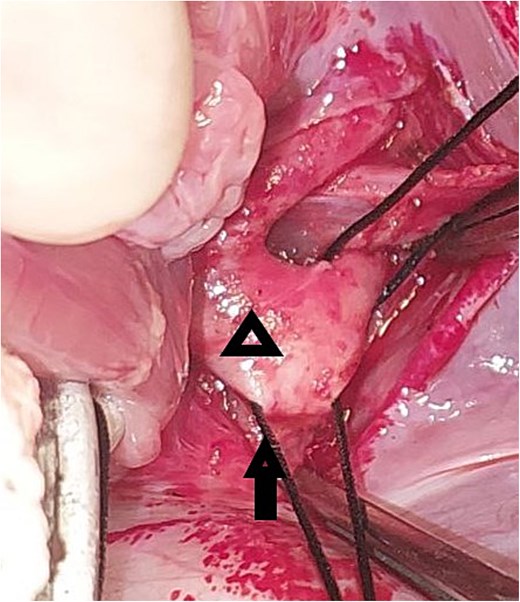

A 20-day-old boy with an unremarkable perinatal history was referred to the pediatric emergency department with respiratory distress. The physical examination revealed poor general condition and central cyanosis. The pulses were bounding in both brachial arteries but the femoral arteries were not palpable. A systolic murmur grade 4/6 was heard along the left sternal edge. The liver was enlarged 2 cm below the costal margin. Transthoracic echocardiography (TTE) was performed and revealed infracardiac TAPVC with associated CoA. Computed tomography angiography (CTA) confirmed the diagnosis of CoA (Fig. 1), and for technical issues, the pathway of CPC was not apparent on CTA. TTE was repeated and the drainage of the CPC into the portal vein was confirmed. The heart team at our hospital decided for urgent surgical repair. At first, the repair of CoA was performed through left thoracotomy with patch plasty technique since the stenosis was too long, and it was not possible to perform resection and end-to-end anastomosis. Then, through median sternotomy, the pericardium was opened, and a total cardiopulmonary bypass (CPB) was prepared. The heart was arrested with an antegrade cold blood cardioplegic solution. The CPC was seen behind the pericardium (Fig. 2). The VV was descending crossing the diaphragm, and it was dissected and controlled (Fig. 3). The heart was lifted out of the pericardium and a long incision was made in LA, and a parallel incision was made in the CPC (Fig. 4). A wide anastomosis was performed between these two incisions thus connecting the CPC into LA. The VV was permanently closed. RA was opened, and a small ASD was closed. The remainder of the operation was completed uneventfully. The patient was weaned off the CPB with stable hemodynamic conditions on low-dose inotropes (milrinone, epinephrin). Postoperative TTE showed normal pulmonary venous drainage without any gradient across the anastomosis, and excellent repair of CoA. After 48 hours on mechanical ventilation, the patient was extubated, and discharged from the ICU after 5 days. On one year follow-up, the patient was with normal growth, and in very good general condition without any complaints. TTE during the follow-up period revealed normal flow in the pulmonary veins.

Intraoperative image showing the pulmonary venous confluence after lifting the heart out of the pericardium: The triangle points to the pulmonary venous confluence, and the arrow points to the vertical vein that crosses the diaphragm.